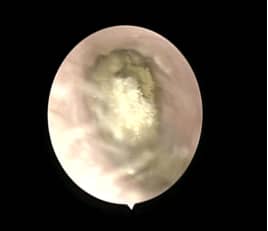

耳真菌感染称为外耳道真菌病或霉菌性外耳道炎,是真菌侵入外耳道或外耳道内的条件致病性真菌,在适宜的条件下繁殖,引起的外耳道的炎性病变。

耳道真菌病可以发生在任何年龄,以成人为多见,是一种慢性或亚急性传染病,为真菌进入外耳道后繁殖生长所引起的一种皮肤感染,多局限于外耳,也可经穿孔的鼓膜侵入中耳及乳突术腔。

2、由于真菌大量繁殖,堆积形成团块可阻塞外耳道引起阻塞感。

3、真菌团块刺激,外耳道可有少量分泌物,患者感外耳道潮湿。

4、外耳道的脱落上皮和菌丝体等混合、阻塞外耳道而影响听力的传导,或与鼓膜相碰撞摩擦而产生声响,患者可有听觉障碍,耳鸣,甚至侵袭鼓膜导致眩晕。